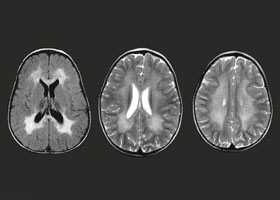

МРТ головного мозга необычайно высоко чувствительна к дисмиелогенным нарушениям, но не очень специфична в плане дифференциальной диагностики внутри группы. При всех этих патологиях на Т2-взвешенных МРТ и МРТ, отражающих протонную плотность, видны гиперинтенсивные поля в белом веществе.

Следствием метаболической аномалии является разрушение миелина оболочек нервных стволов и проводящих путей, гибель нейронов с замещением их разрастающейся глиальной тканью. Морфологически лейкодистрофия характеризуется диффузными и симметрично расположенными в полушариях головного мозга зонами гибели миелина, скоплением продуктов миелинового распада, усиленной пролиферацией глии. В отдельных нозологических вариантах лейкодистрофия имеет специфическую морфологическую картину — метахроматическое или суданофильное окрашивание продуктов миелинового распада, скопление в зонах демиелинизации глобоидных клеток и т. п.

С целью диагностики вида метаболической аномалии проводится целый ряд биохимических тестов с определением уровня ферментов и накапливающихся метаболитов. Очаги демиелинизации хорошо визуализируются при помощи МРТ, могут быть обнаружены и на КТ головного мозга. Обычно демиелинизация видна на МРТ головного мозга еще до клинической манифестации лейкодистрофии. Благодаря развитию генетики, лейкодистрофия имеет разработанную ДНК-диагностику, а отдельные ее формы (метахроматическая, адренолейкодистрофия, глобоидно-клеточная) — возможность пренатального диагностирования.